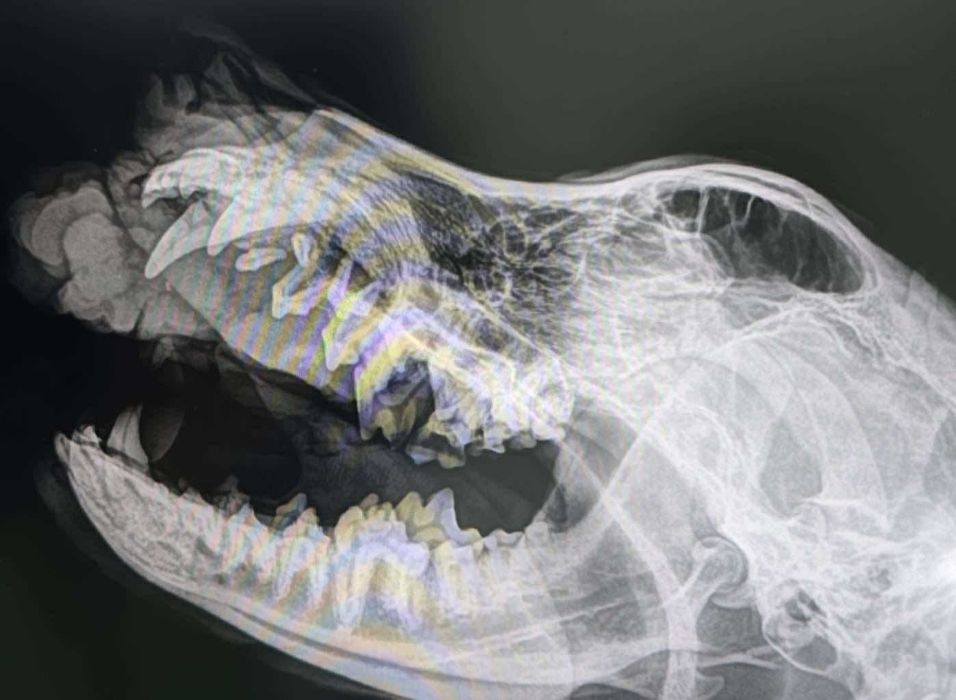

Leider gibt es traurige Nachrichten von ARON aus Rumänien. Bei dem tollen Schäfi wurde ein Tumor diagnostiziert. In der Klinik wurden Röntgenaufnahmen gemacht, die gezeigt haben, dass sich bereits Lungenmetastasen gebildet haben.